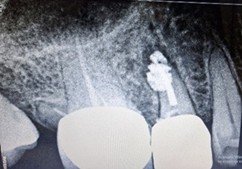

A 55-year-old woman presented to our department with a ten-day history of unrelenting pain in the upper right posterior region. Her prior medications provided no relief. Clinical examination of tooth 15 revealed mild vestibular swelling beneath a metal-free crown. Periapical radiography confirmed a large radiolucent area consistent with a periapical abscess. An earlier attempt at access had been made, with canals negotiated and prepared, but treatment remained incomplete.

We immediately initiated root canal therapy. Once the gingival swelling subsided, Metapex was placed as an intracanal medicament. The patient experienced no inter-appointment discomfort, and serial radiographs over five months demonstrated complete resolution of the lesion with restoration of healthy periapical bone.

Figure 1: Pre operative IOPA revealing incomplete root canal treatment with crown placement wrt 15.

Figure 1: Pre operative IOPA revealing incomplete root canal treatment with crown placement wrt 15. Figure 2: Root canal initiated through crown and metapex placed.

Figure 2: Root canal initiated through crown and metapex placed. Figure 3: Post operative IOPA after 2 months reveals marked reduction in the lesion.

Figure 3: Post operative IOPA after 2 months reveals marked reduction in the lesion. Figure 4: Post op IOPA after 5months reveals complete healing of periapical lesion, crown removal done, root canal master cone IOPA confirms.

Figure 4: Post op IOPA after 5months reveals complete healing of periapical lesion, crown removal done, root canal master cone IOPA confirms. Figure 5: Post obturation IOPA.